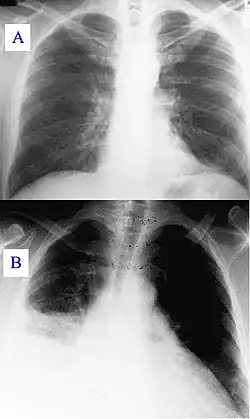

During its course, the disease can progress to an atypical pneumonia, which can result in a life-threatening acute respiratory distress syndrome, whereby such symptoms usually occur during the first four to five days of infection.[6]

Q fever can cause endocarditis (infection of the heart valves) which may require transoesophageal echocardiography to diagnose. Q fever hepatitis manifests as an elevation of alanine transaminase and aspartate transaminase, but a definitive diagnosis is only possible on liver biopsy, which shows the characteristic fibrin ring granulomas.[21]